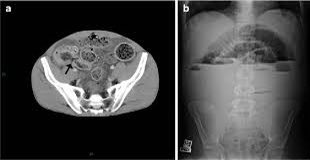

ويستخدم في متلازمة انسداد الامعاء

Distal intestinal obstruction syndrome